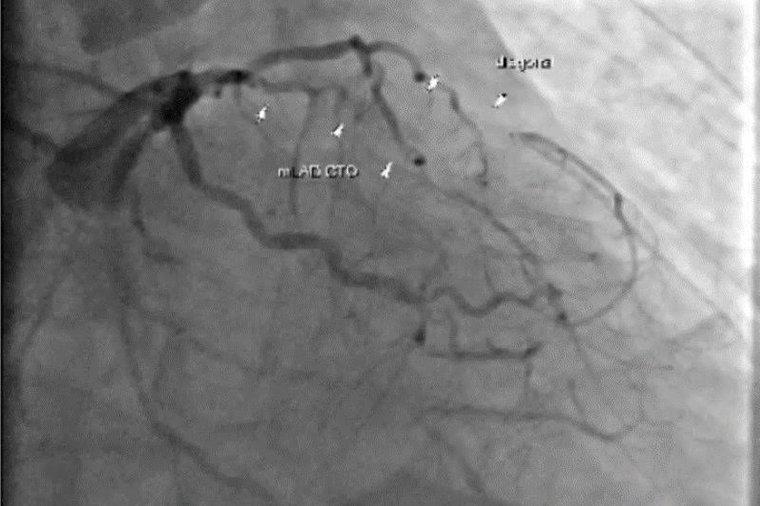

▲個案在心導管檢查中,發現3條冠狀動脈全數堵塞,病況危急。(圖/台北慈濟醫院提供)

楊凱文說,個案長期以來都有冠狀動脈狹窄的問題,曾接受過支架放置手術,理論上應持續服用抗血小板藥物,但卻因自行停藥許久,導致心臟血管隨時間慢慢阻塞,進而造成心肌缺血壞死與心臟衰竭。對於心臟嚴重衰竭的病人而言,移植是唯一的救命方式。特別是個案在3條冠狀動脈全部阻塞,左心室有巨大血栓,且心臟肌肉大範圍壞死的情況下,病情相當危急。手術團隊先進行冠狀動脈繞道手術與血栓清除,並以人工補片重建心臟壁,在手術中還同步放置暫時性左心室輔助器(LVAD),協助心臟輸出血流。